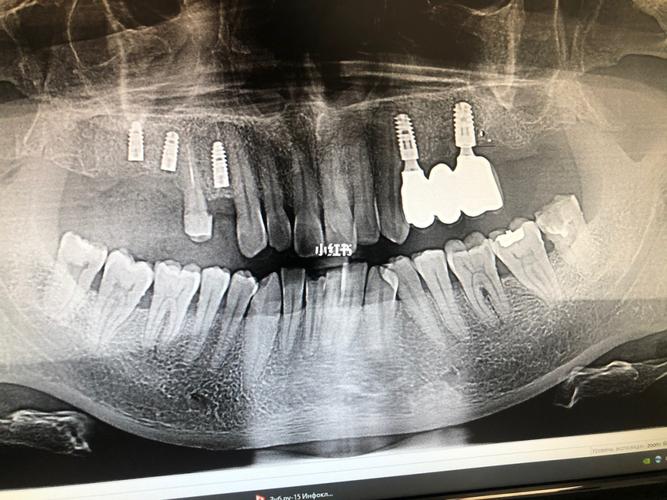

帮忙看看刚种的三颗是否歪了,感谢!_种植牙_医疗健康

种植牙牙体种歪了图片